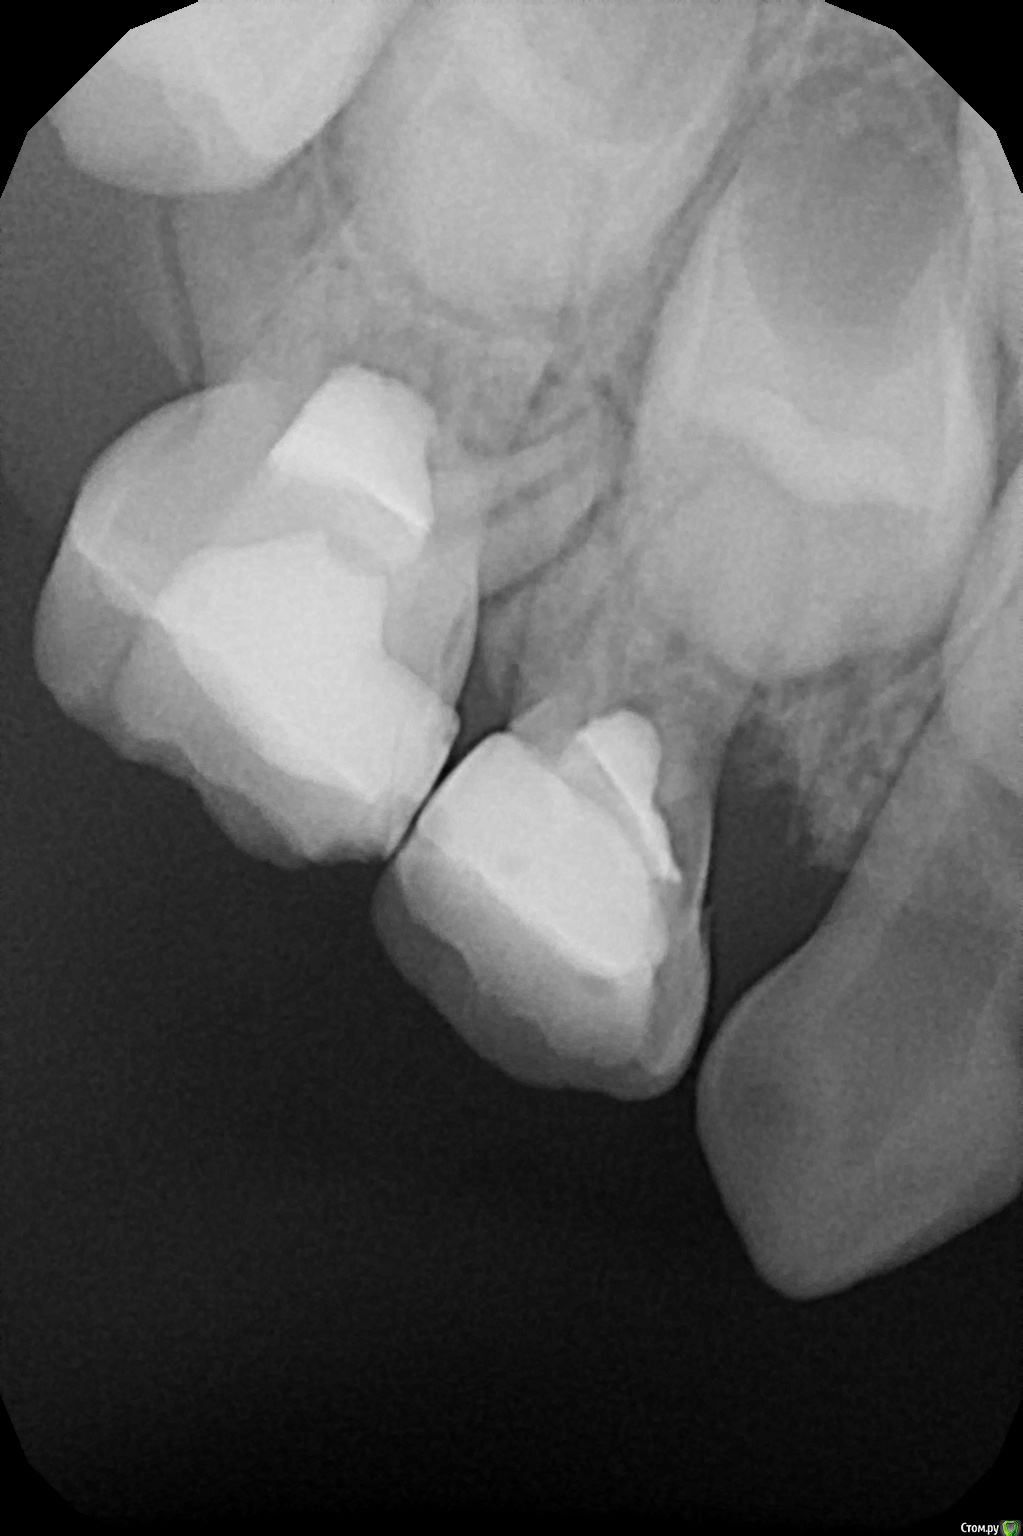

crown Опубликовано 1 сентября, 2016 Поделиться Опубликовано 1 сентября, 2016 Все народ перехожу на экстирпацию, разочаровался я в методе витальной ампутации. Перепробовал все: кальций, цоэ, пульпотек, мта и даже резорцин) но увы, большой процент осложнений. Вот один из последних пациентов, 8.5 пролечил с триоксидентом, прошло 3-4 месяца, гангренозный пульпит, причем там бал кариес!(( 8.4, лечил год-полтора назад, в бифуркации беда, надо перелечивать, 5.4 - 2 года с момента лечения сгрызся медиальный корень. А парню только 5 лет. Читал несколько статей, где проводили лечение пульпита разными материалами, а потом сравнивали в динамике, так вот процент успеха в первые два года 96%!!!! а с мта так вообще 100%!! причем без коффердама. Не знаю может я что то делаю не так, может они что то делают так)) но мой процент гораздно ниже. Ссылка на комментарий